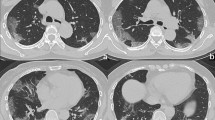

The clinical and CT characteristics of patients who progressed to severe COVID-19 (progressive group) and patients who did not (stable group) in the derivation cohort are presented in Table 2. Compared with those in the stable group, patients in the progressive group were significantly older (median age, 58 vs. 41 years old, P = 0.001) and more likely to have underlying hypertension (P = 0.004). But no significant difference was found in gender, exposure history, smoking history, and other co-morbidities including diabetes, chronic obstructive pulmonary disease (COPD), cardiovascular disease, cerebrovascular disease, and chronic hepatitis B infection between the two groups. The main clinical symptoms between the two groups were not statistically different, while slightly more patients manifested anorexia (P = 0.088), diarrhea (P = 0.065), and shortness of breath (P = 0.088) in the progressive group. There was no significant difference in percutaneous oxygen saturation on admission between the two groups (P = 0.110). Patients in the progressive group had lower baseline lymphocyte count and albumin, and higher NLR, aspartate aminotransferase, lactic dehydrogenase, and C-reactive protein (all P < 0.05). The major CT features of COVID-19 pneumonia patients were bilateral, peripheral or mixed distributed GGO, consolidation, and GGO with consolidation (Fig. 2a–f). Patients in the progressive group had more lobes and segments involved, with a higher proportion of crazy-paving sign and higher CT severity score (Supplementary Fig. 1a) compared with those in the stable group (all P < 0.05). However, no significant difference was found in hospital length of stay (P = 0.398) and duration of viral shedding after illness onset (P = 0.087) between the two groups.

a Subpleural patchy areas of GGO with crazy-paving sign in the right middle lobe. b Multiple patchy areas of consolidation in the right middle lobe, left upper lobe, and bilateral lower lobes and air bronchogram in the right middle lobe. c Multiple patchy areas of organizing pneumonia in the right middle and lower lobes on the sagittal image with CT severity score of 9 for the right lung. d Bilateral and peripheral multiple patchy areas of GGO with reticular and intralobular septal thickening. e Multiple mixed distributed pure GGO, GGO with consolidation, and interlobular septal thickening in bilateral lungs. f Bilateral multiple patchy and thin areas of GGO in the posterior parts of the lungs.